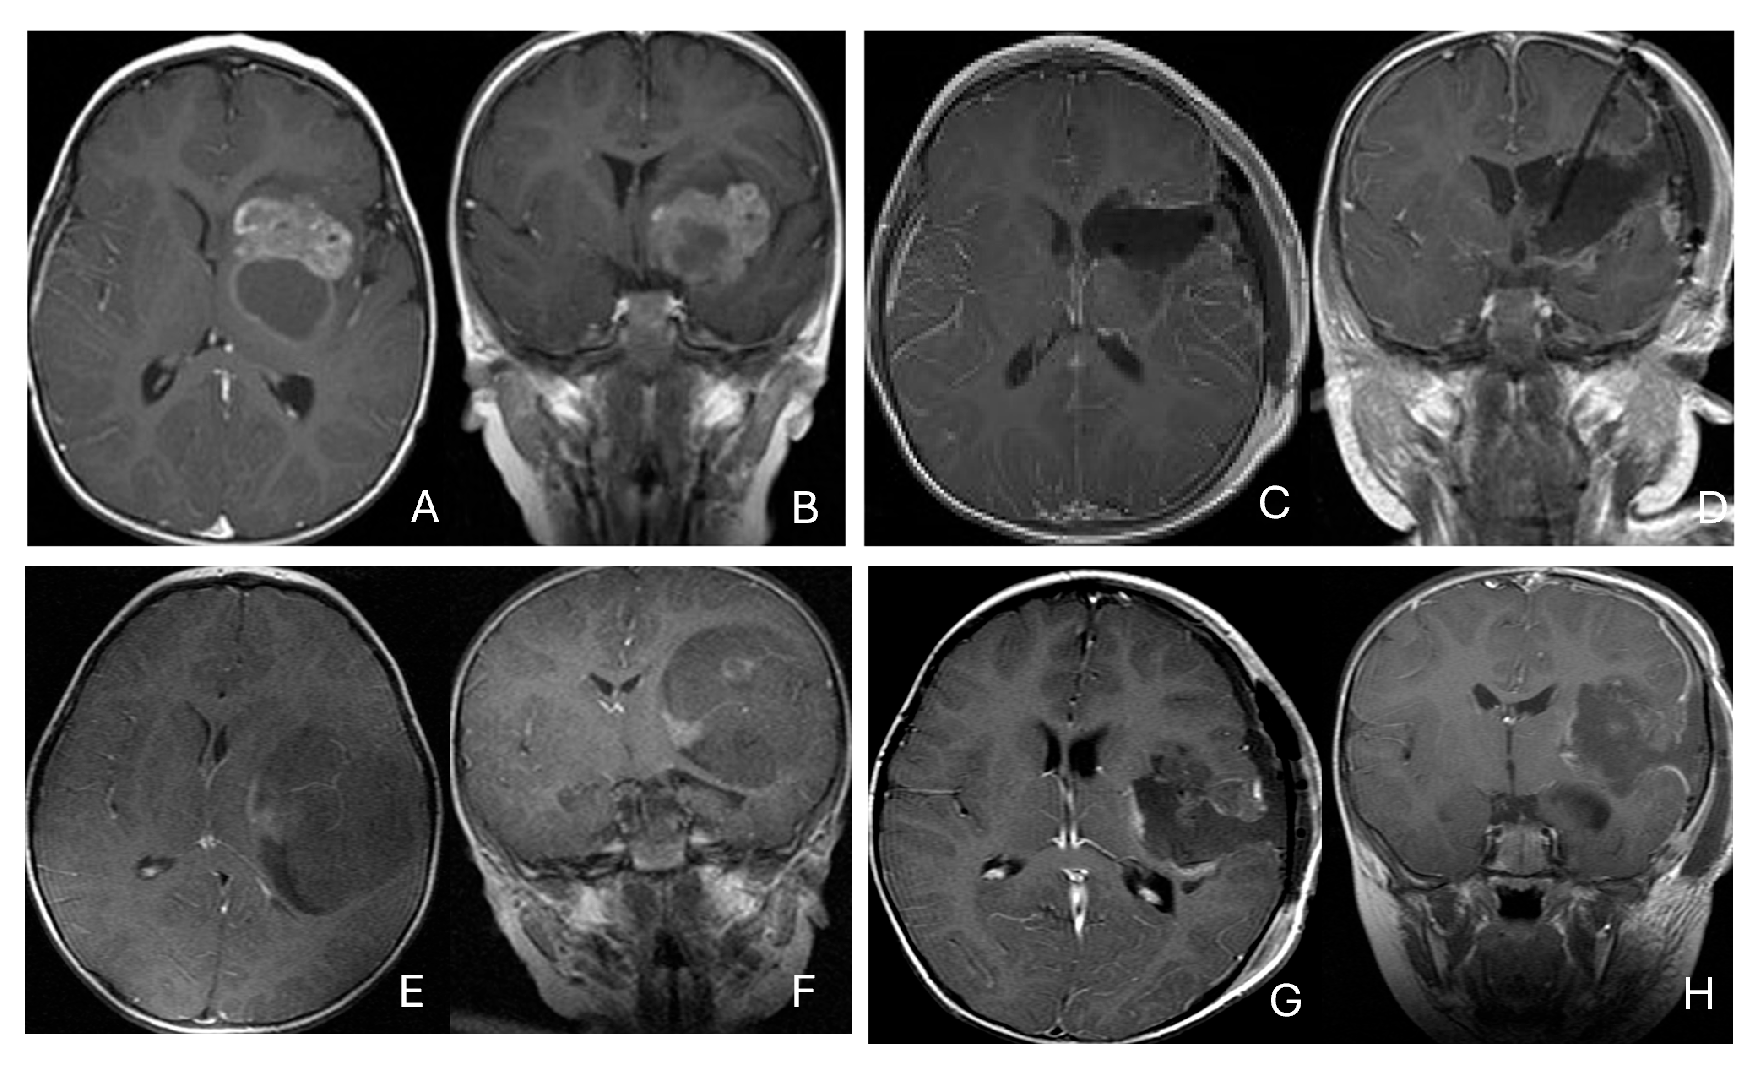

Figure 2.

Multi-lobe ATRT. (A–D): A 3-year-old boy with a heterogeneous frontotemporal ATRT with encasement of Sylvian vessels on MR images ((A), axial; (B), coronal). Intraoperatively, the tumor replaced both the frontal and temporal opercula, extended to the anterior, and displaced/encased branches of the middle cerebral artery. Postoperative MR images after resection ((C), axial; (D), coronal) confirm multilobe involvements. (E–H): of a 30-month-old boy with a temporoparietal cystic ATRT crossing the Sylvian fissure shown on T2-weighted MR images ((E), axial; (F), coronal). Correlative intraoperative findings and imaging demonstrated the tumor extending from the temporal lobe into the posterior frontal lobe across the Sylvian fissure and encasing middle cerebral artery branch. Post-resection MR images ((G), axial; (H), coronal) show a resection cavity spanning the temporal and posterior frontal opercula.

Three tumors were predominantly located within the ventricle, two within the lateral ventricle and another within the third ventricle (Figure 4). None appeared to arise from the choroid plexus or as pedunculated lesions from the ependymal layer; rather, operative and imaging features supported a paraventricular origin because of diffuse attachment to the ventricular wall. Two large hemorrhagic hemispheric tumors extended into the lateral ventricle. These paraventricular ATRT extends into the lateral ventricle (Figure 5).

Figure 4.

Intraventricular ATRT. (A–D): A 7-month-old boy with ATRT within the left lateral ventricle with associated hydrocephalus shown on MR images ((A), axial; (B), coronal; (C), sagittal). Note irregular peritumoral cysts and ependymal invasion which was confirmed at surgery. Postoperative MR image ((D), axial) shows a gross-total resection. The patient had a history of rhabdoid tumor predisposition syndrome. (E–H): A 34-month-old boy with MR images ((E), axial; (F), coronal; (G), sagittal) showing an intraventricular mass at the anterior horn based on the septum pellucidum. ATRT was originated at the junction of the septum pellucidum. Post-contrast MR ((H), axial) confirms resection. (I–L): Post-contrast MR images ((I), axial; (J), coronal; (K), sagittal) of a 3.5-year-old boy demonstrate a large, enhancing third ventricular ATRT with partial extension into the lateral ventricle. The lesion was removed via an interhemispheric transcallosal approach ((L), sagittal).

Figure 5.

Paraventricular ATRT with ventricular extension. (A–D): A 3-month-old girl who presented with emesis followed by acute decerebrate posturing. Post-contrast MR images ((A), axial; (B), coronal; (C), sagittal) reveal a large hemorrhagic mass in a deep centrencephalic location. Postoperative MR ((D), axial) shows a focal dilation of the lateral ventricle after subtotal resection of a parietal para-ventricular ATRT.

Three patients presented with massive subdural/parenchymal masses involving both cerebral hemispheres across the falx cerebri; two bi-frontal and one in bi-occipital (Figure 6). These tumors appeared to originate within the cerebral hemispheres and permeate or traverse the falx cerebri, resulting in bilateral disease.

Figure 6.

Bi-hemispheric ATRT. (A–E): MR images ((A), axial; (B), coronal; (C), sagittal) of a 4-year-old boy show a bifrontal ATRT crossing the falx cerebri, with heterogeneous enhancement. The corpus callosum is compressed posteriorly. At surgery, left frontal component invades and permeates through the falx with extension into the right subdural space. Postoperative images after bifrontal craniotomy ((D), axial; (E), coronal) show tumor resection. Bi-occipital hemispheric ATRT. (F–J): MR images ((F,G), axial; (H), coronal) of a reveal a 22-month-old girl large, inhomogeneous left occipital lobe mass crossing the midline into the right occipital lobe. The lesion invades the posterior falx cerebri and extends into the medial occipital lobe of the right side. A highly vascular tumor was resected via a left occipital craniotomy; the right occipital component was not removed with concern of blindness due to preexisting right homonymous hemianopia. She received chemoradiation with durable disease resolution for over 15 years, as shown on follow-up post-contrast MR ((I), axial; (J), coronal).